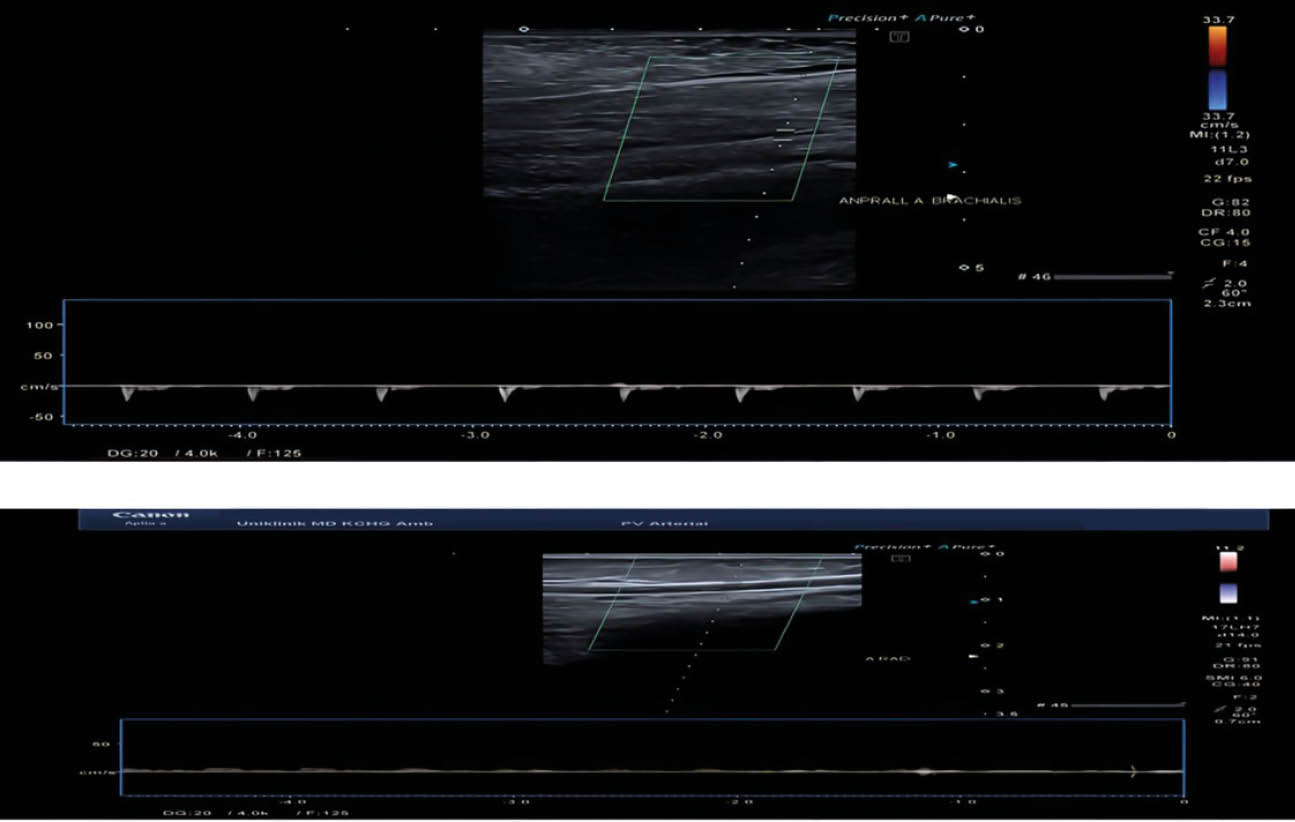

Abb. 3 (A – C): Sonografie-Kontrolle nach geschlossener Reposition und Drahtspickung der Humerusfraktur

(Fotos: Arbeitsbereich Gefäßchirurgie, Klinik für Allgemein-, Viszeral-, Gefäß- und Transplantationschirurgie, Universitätsklinikum Magdeburg A. ö. R.)

A) Doppler-Sonografie am ersten postoperativen Tag – zeigt Verschlechterung der systolischen Spitzenfrequenz (FS) der A. radialis dextra

C) Doppler-Sonografie am Entlassungstag – zeigt Verbesserung des FS der rechten Armarterien.

B) Farbkodierte Duplex-Sonografie am ersten postoperativen Tag – zeigt Anprall der A. brachialis dextra und Verschlechterung des Abflusses in die A. radialis detxra